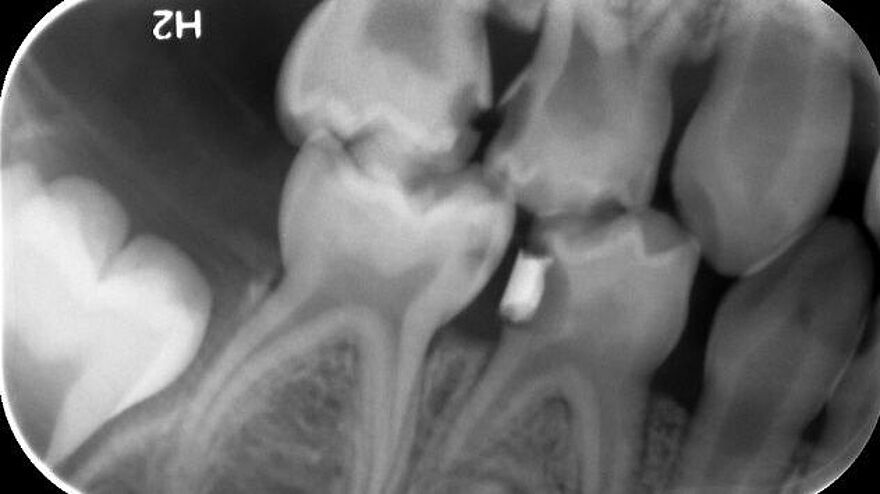

Dieses Milchgebiss wurde fachgerecht saniert. Die Karies ist verschwunden. Die Milchzähne werden erhalten, bis sie von den bleibenden Zähnen ersetzt werden. Dafür wurden auch Milchzahnkronen eingesetzt. Jetzt sind beste Bedingungen für eine effiziente Prophylaxe gegeben.